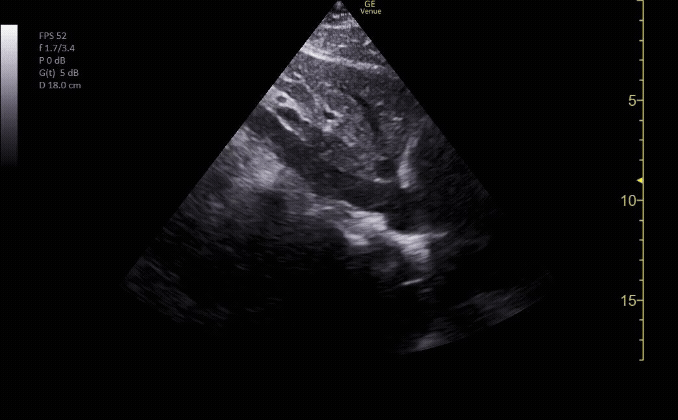

Parasternal long view showing the right ventricle, left ventricle, left atrium mitral valve, aortic root, and descending aorta.

c/o Kyle Ackerman, MD